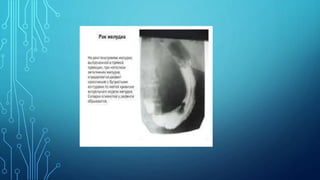

6. Fluoroscopy of the stomach: the main

symptoms are filling defect, the presence of

aperestaltic zones. Apithetic relief of the

mucous membrane, local thickening or

breakage of the folds of the mucous membrane.

Diagnostics 1. Complaints 2. Anamnesis 3.Palpation 4. Study of gastric contents 5. Blood test 6. Fluoroscopy of the stomach: the main symptoms are filling defect, the presence of aperestaltic zones. Apithetic relief of the mucous membrane, local thickening or breakage of the folds of the mucous membrane. 7. Gastroesophagoduodenoscopy 8. Biopsy